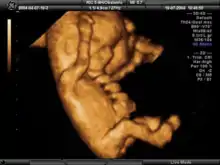

La ecografía obstétrica es un método médico usado para determinar la presencia de embarazo y conocer las condiciones del embrión o feto, así como de la placenta, útero, cuello del útero y líquido amniótico. La ecografía es un procedimiento de diagnóstico que emplea el ultrasonido para crear imágenes bidimensionales o tridimensionales. Un pequeño instrumento (muy similar a un micrófono) llamado transductor emite ondas de ultrasonidos. Estas ondas sonoras de alta frecuencia se transmiten hacia el área del cuerpo bajo estudio y se recibe su eco, el cual es procesado por una computadora que muestra una imagen de los órganos o el feto sobre los que ha incidido el ultrasonido.

Es el método más seguro para conocer el estado general del embarazo y, según las semanas de gestación, tiene sus indicaciones específicas. El examen es por imágenes. Las ondas sonoras reflejadas en el vientre materno permiten ver el desarrollo del feto dentro del útero de la madre. También es utilizado para ver los órganos pélvicos de la madre durante su embarazo. La ecografía obstétrica no emplea radiación ionizante.